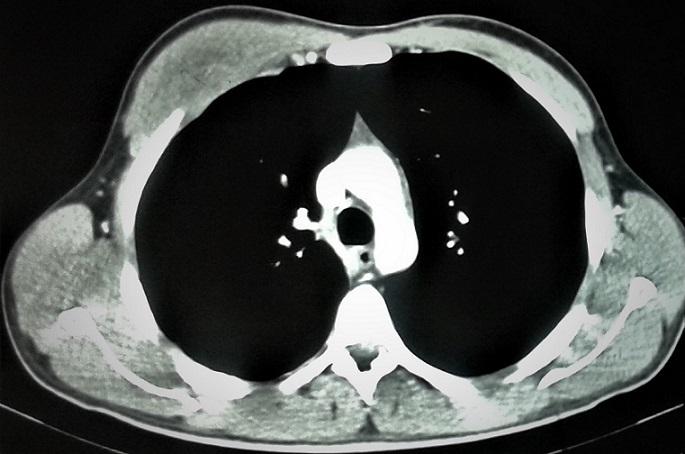

Soft tissue tuberculosis is one of the rare forms of extrapulmonary tuberculosis. Furthermore, isolated muscular tuberculosis is exceptional. We here report the original case of a young immunocompetent patient with isolated muscular tuberculosis involving major pectoralis muscle. The diagnosis was mainly based on histology. The patient was successfully treated with anti bacterial therapy only. This rare case study has been combined with a literature review.

摘要

软组织结核是肺外结核的罕见形式之一。此外,孤立性肌肉结核更是罕见。我们在此报告一例原本健康的年轻患者发生累及胸大肌的孤立性肌肉结核的病例。诊断主要基于组织学检查。该患者仅通过抗菌治疗即获成功治愈。本罕见病例报告还结合了文献综述。